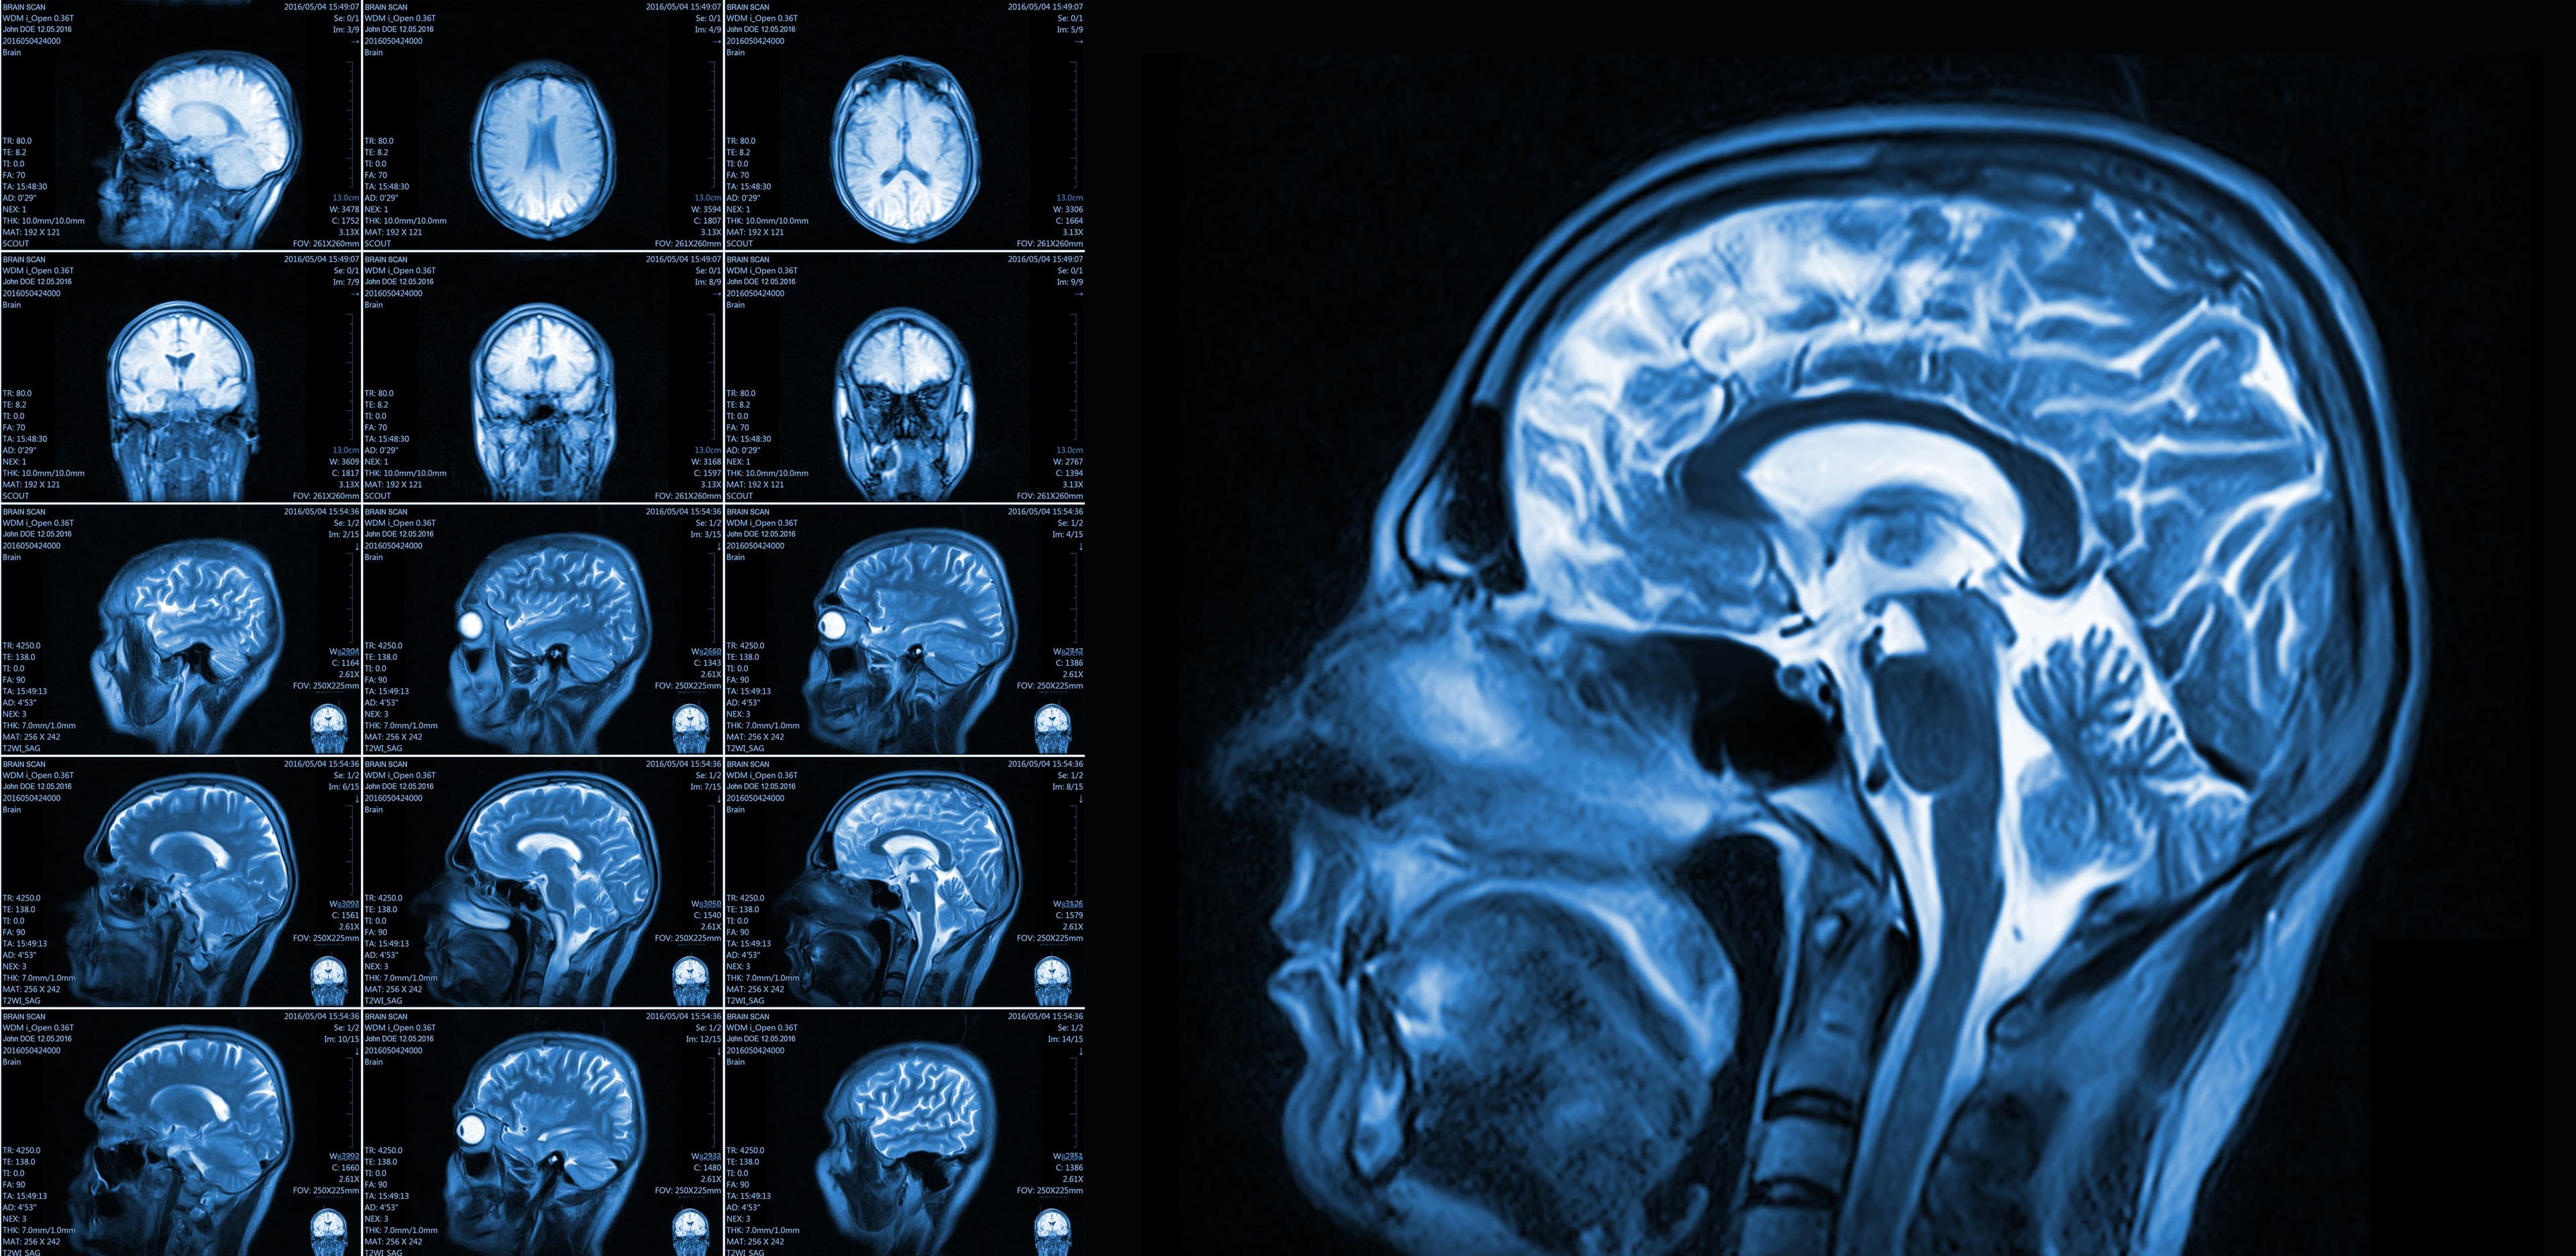

Detailed Explanation of Location-Specific Imaging

Brain Mapping Solutions uses cutting-edge MRI and DTI post-processing technology to deliver detailed images of brain injuries. This allows healthcare professionals to pinpoint the exact location of damage, providing them with the data they need to tailor treatment plans to each patient's specific needs.